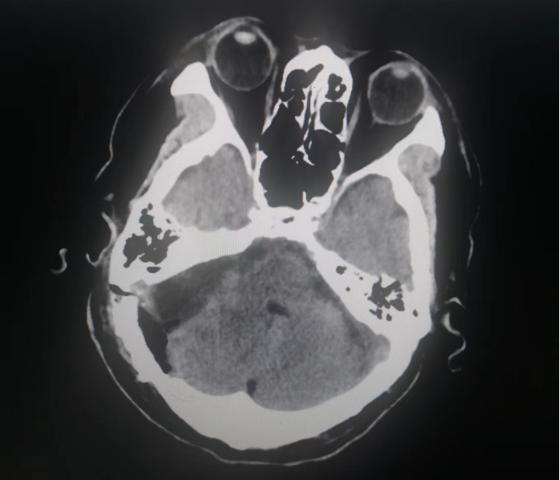

患者入院后,头颅MR检查后发现,小脑右侧长了巨大肿瘤,直径约6公分,患者家属收到不小的惊吓。患者4年前曾做过一次头颅核磁共振,当时肿瘤较小,考虑到患者已经88岁,家人还是决定保守观察,没想到如今,它已经长大到足足有一个土豆那么大,而且患者头晕较重,反复恶心、呕吐,卧床不起,因此必须进行手术,才能解决患者病症。

患者家属反复考虑、综合思量后,决定接受手术治疗。神经外科二病区主任白西民及团队进行综合评估,术前讨论,研究患者肿瘤位置、毗邻关系及心肺状况,制定周密手术方案。联合呼吸科、心内科、麻醉科及重症医学科等学科会诊,研究制定详细手术方案及应急预案。